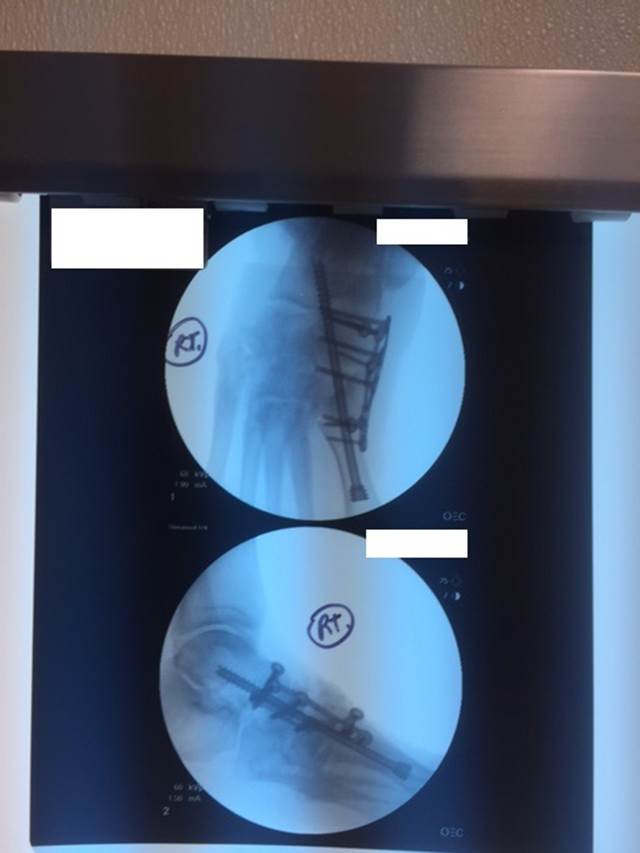

"Surgical misadventure" by another surgeon about 8 years ago. The wrong fixation was used for a flatfoot repair, & the deformity was not corrected. Patient came in with severe foot & ankle pain, with no arch at all. She was unable to play with her grandchild because the pain was so bad, & because she felt unsteady. The old hardware was removed, a lateral calcaneal lengthening osteotomy was performed along with a medial column/1st ray realignment. The ankle was painfully arthritic, & patient elected a total ankle replacement vs. an ankle fusion. She is now able to walk pain free & play with her grandchildren!